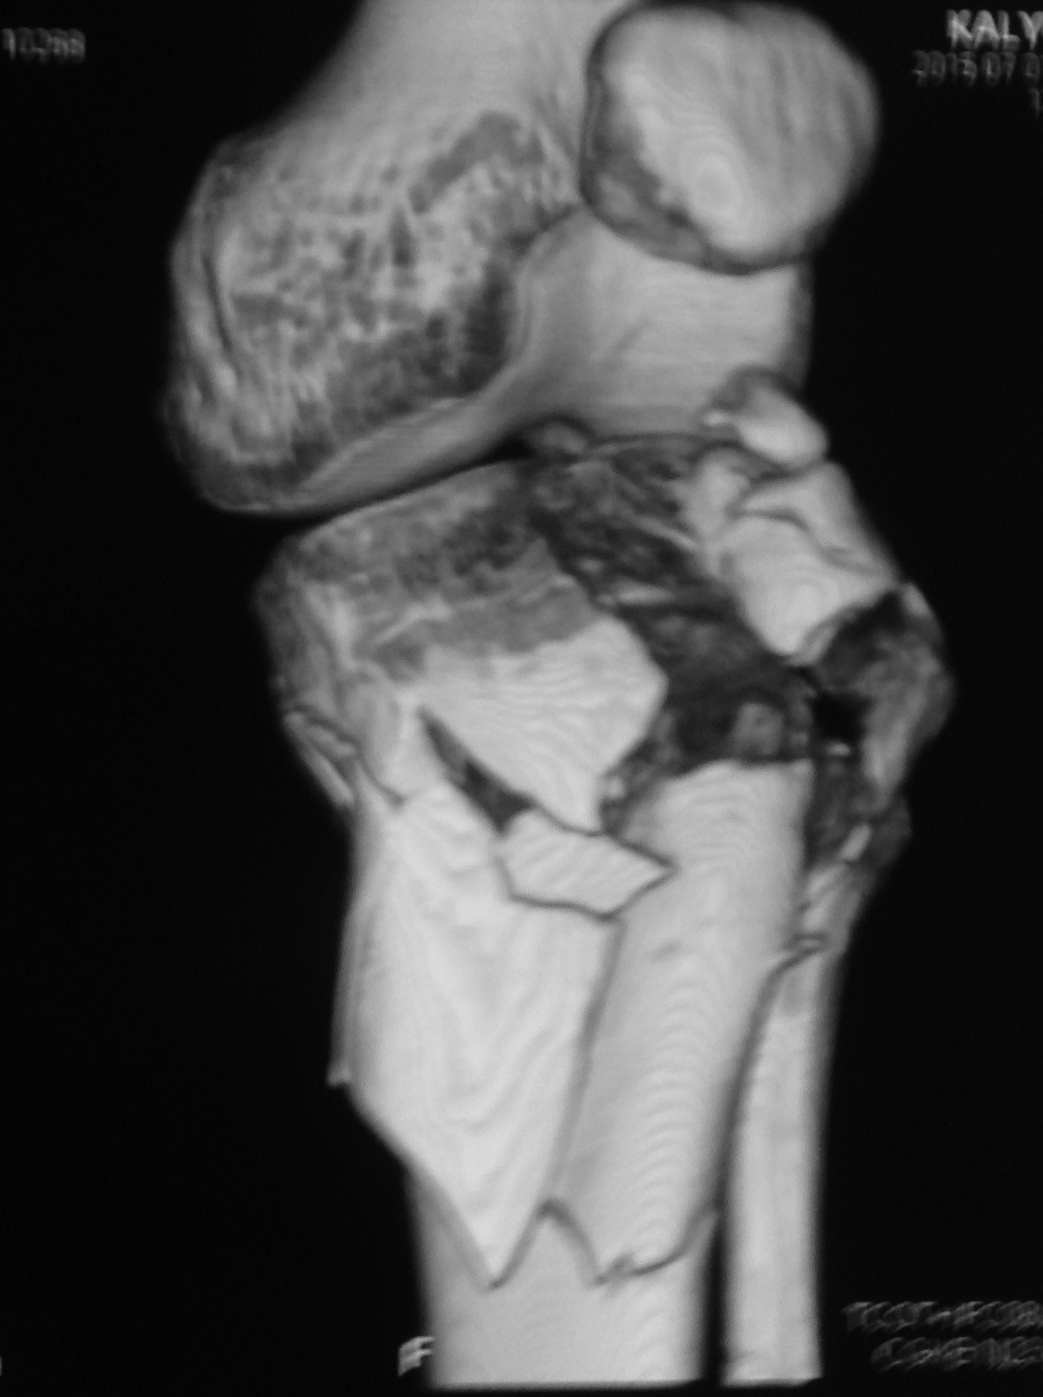

[Ortho] перелом проксимальной тибии + вывих бедра

Высокоэнергетическая травма около недели назад, мужчина 39 лет

По месту поступления вывих бедра вправлен, ПХО раны открытого перелома

б/б кости, скелетное вытяжение. В настоящее время рана заживает неплохо,

небольшое количество серозно-геморрагического отделяемого, состояние

мягких тканей неплохое. Планируем остеосинтез плато из 2-х доступов по

заживлению раны.

1 смущает фрагмент плато в проекции раны, насколько удобно его будет

ловить, попробовать полечить в аппарате + винты

закрыто?

2 часть задней стенки в суставе, такое впечатление, что она больше ямки

и подвывихивает сустав или это ошибочное впечатление?

3. насколько целесообразно искать этот фрагмент во впадине и пытаться

засинтезировать задний край при наличии довольно выраженного FAI?